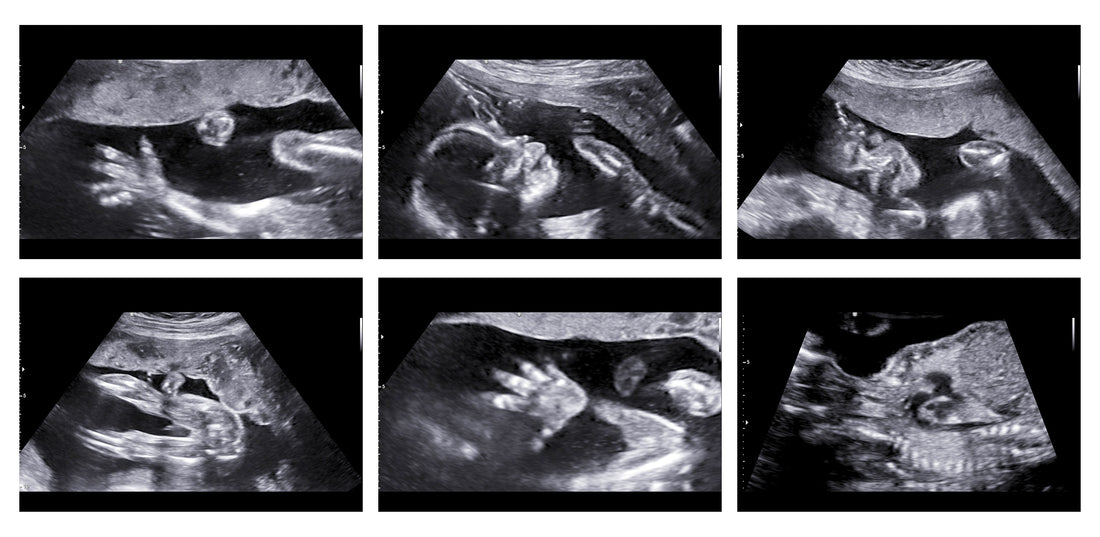

The precise transmission and reception of sound waves by the transducer is essential for producing high-quality ultrasound images. The transducer needs to make good skin contact for this to occur, and here is where ultrasonic gel comes into play. The gel provides an even, smooth surface on the skin that makes it possible for the transducer to move over it without encountering any obstacles. This guarantees that sound waves are precisely transmitted and received by the transducer, producing sharp, high-resolution pictures.

Air pockets between the skin and the transducer, which can obstruct the transmission of sound waves, can also be reduced with the aid of ultrasound gel. Air pockets can cause sound waves to reflect and refract, distorting the visuals and lowering their quality. Ultrasound gel aids in removing these aberrations and enhancing picture accuracy by saturating these air pockets.